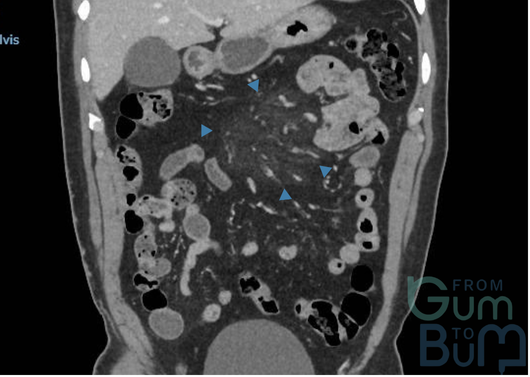

16 yo male attended with worsening RIF pain and guarding.  He reports having asthenia and weight loss over the last month.  He has not had diarrhoea.  His CRP is 110mg/l,  Hb is 10.2mgdl and white cells are 13000.

In view of suspicion of inflammatory process, a CT scan is done after a negative abdomen US for appendicitis.  CT confirms terminal ileitis confined to about 4cm of distal ileum.   Colonoscopy is performed with the attached image in the ileum, being the rest of the colonic mucosa and perianal area normal.

The CDA score is 250 (moderate)